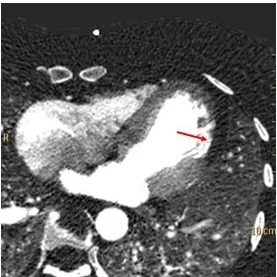

CTA shows no dissection. But look closely, and on the conventional images you can see relatively sharply defined endocardium in the lateral wall of the left ventricle, while the rest of the endocardium is fuzzy. I like this previously undescribed sign, it helps me detect cardiac hypoperfusion on non-gated scans.

Conventional CT: Focal sharply defined endocardium (red arrows). This is a very good sign for an acute MI on non-gated chest CT scans.